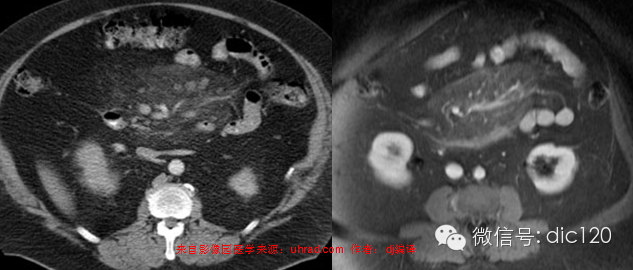

5、肿瘤

最常累及肠系膜的肿瘤是非何杰金氏病淋巴瘤(NHL),NHL常导致淋巴结肿大成团而呈“三明治”征,NHL也是边缘清楚的肠系膜混浊最常见的病因,化疗使受累淋巴结缩小后易与显示,受累肠系膜呈薄纱状,与全身性疾病引起的肠系膜水肿不同,病变完全局限于原肿大淋巴结的区域,尽管有乳糜腹水的报道,但合并腹水并不常见,对照化疗前肠系膜区和覆膜和膜膜后淋巴结肿大可作出正确诊断,何杰金氏病极少累及肠系膜,NHL累及小肠系膜远较其他系膜多见。侵犯肠系膜的其他肿瘤包括:胰腺癌、结肠癌、乳腺癌、胃癌、类癌、黑色素瘤、白血病、间皮瘤及卵巢癌等,偶尔中央淋巴管阻塞引起肠系膜水肿,发现肠系膜根部的肿块常提示中央淋巴管阻塞。肿瘤半纤维化和淋巴水肿可类似肠系膜混浊,类癌表现为肿块周围有星样放射状扩展的纤维条索并有结节,常有钙化,这在其他病少见。约1/3肠系膜纤维化增生弥漫浸润肠系膜,尽管组织学表现为良性,但肿块为局部侵蚀性,半数强化较肌肉明显,腹壁纤维增生或纤维瘤常伴有Gardner氏综合症提示此病。